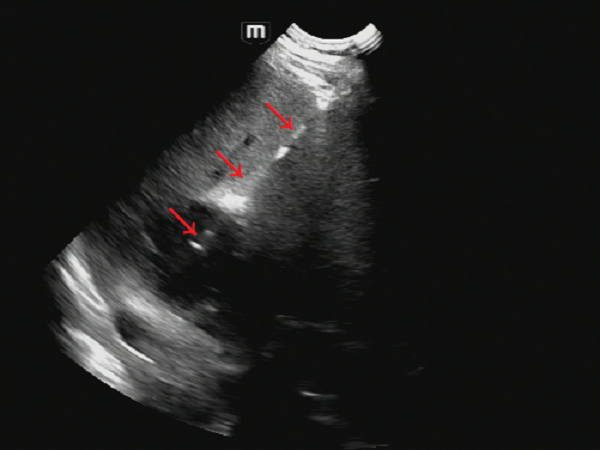

操作过程:患者左侧卧位,对右肝前叶上段脓肿选择穿刺点,常规碘伏消毒后铺巾,超声引导下以1%盐酸利多卡因逐层浸润麻醉至肝包膜,选8F套管针直接穿刺法(一步法)穿刺,超声监视下引流管避开肝内血管及胆管,到达脓腔后拔出穿刺针及支撑管(图2、图3),用注射器抽出脓液10ml后(图4),接引流袋固定。

图2 红色箭头所指白色线条为套管针